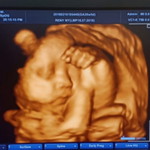

hamil 37weeks